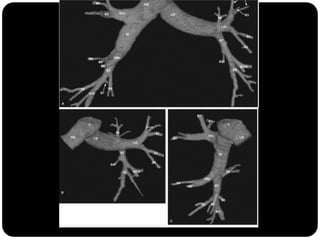

BRÔNQUIOS

PRINCIPAIS

LOBARES

SEGMENTARES

Vias aéreas

Traquéia       Brônquios principais originam-se da traquéia

Brônquios –     na carina;

Bronquíolos    Brônquio direito: ângulo mais obtuso com o

Alvéolos        eixo longo da traquéia;

 Direito(2,2cm) mais curto que o

esquerdo(5cm);

Traquéia      BPD:   BLSD

Brônquios –

BI - BLM

LOBARES              BI – BLID

Bronquíolos

Alvéolos

BPE:   BLSE

BLIE

No pulmão esquerdo

AP AM

JUNTA:

APICOPOSTERIOR

ANTEROMEDIAL basal

Esquerdo



Pulmão direito

Superior: direito

inferior: esquerdo

Traquéia       Pulmão direito:

Brônquios           LSD: anterior, apical e posterior;

      LM: medial e lateral;

      LID: superior, basal medial, basal lateral,

basal anterior, basal posterior;

 Pulmão esquerdo:

     LSE: apicoposterior, anterior,

superior(língula), inferior(língula);

     LIE: segmento superior, basal antero-

medial, basal lateral e basal posterior;